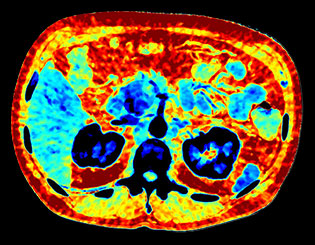

Здесь представлена серия изображений, на которых значения воксела обозначают эффективное атомное число. Эффективное атомное число может быть дробным, обозначающим какой-либо элемент, соединение или смесь. Данное число может отличаться от порядкового номера, указанного в периодической таблице. Единица для обозначения — Z.